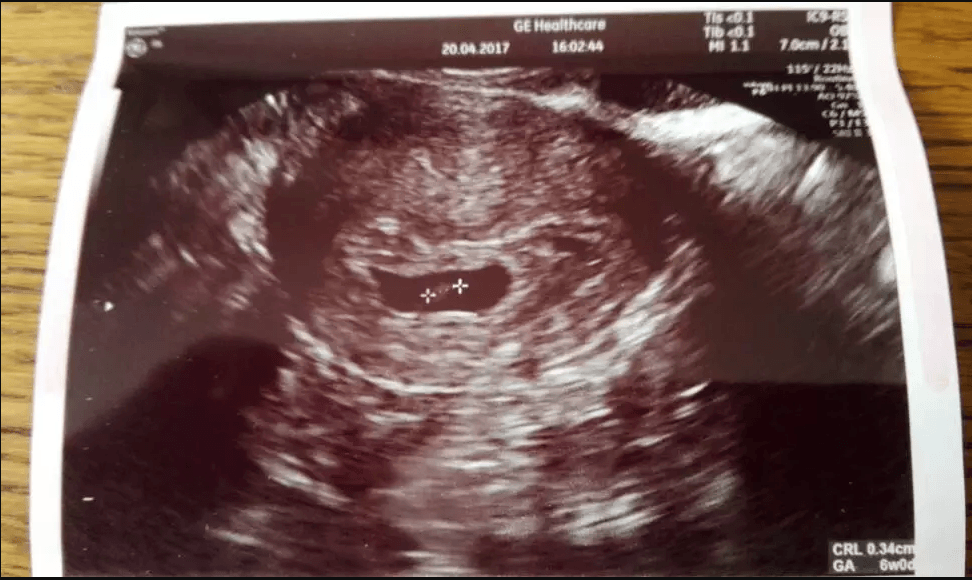

Śliczny !!!!Przedstawiam wam moje cudowne 3mm człowieka.

Zobacz załącznik 803380